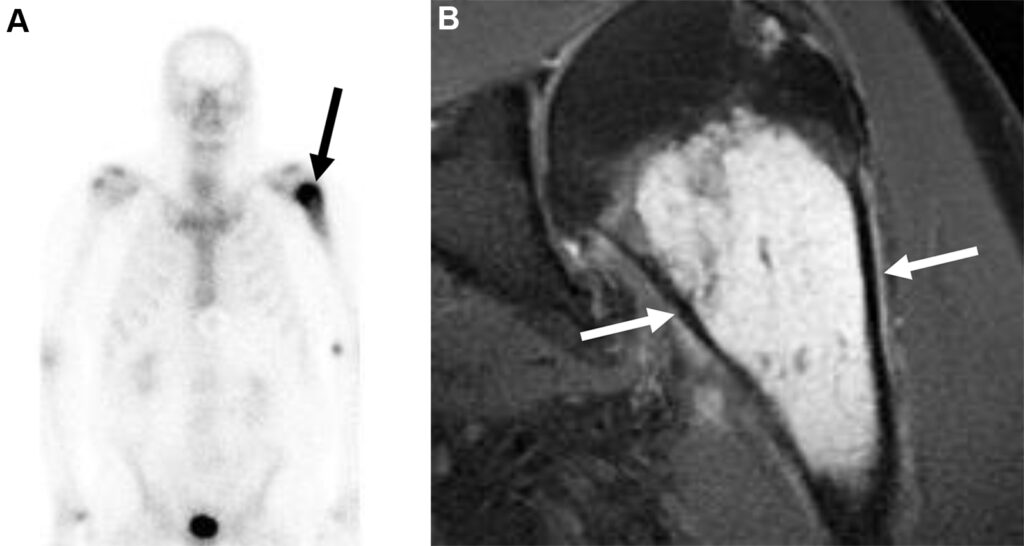

Condrosarcoma in un uomo di 63 anni con dolore progressivo alla parte superiore del braccio sinistro.

L’esame scintigrafico total body evidenzia un’intensa ipercaptazione focale in corrispondenza della metafisi prossimale dell’omero sinistro. I tumori di derivazione cartilaginea (come i condrosarcomi) possono captare avidamente il radiotracciante in base al grado di ossificazione endocondrale, alla presenza di calcificazioni della matrice o alla reazione osteoblastica dell’osso adiacente.

La risonanza magnetica definisce l’anatomia della lesione, evidenziando una massa iperintensa nelle sequenze T2 a livello metafisario, circondata da edema reattivo nei tessuti molli o midollari perilesionali.